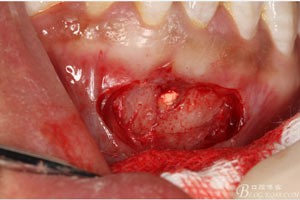

圖7.局部麻醉下,行下前牙唇側(cè)弧形切口,翻瓣可見(jiàn)31唇側(cè)骨壁有缺損,并有根充物暴露

圖8.超聲骨刀去除根尖周?chē)腥竟琴|(zhì)